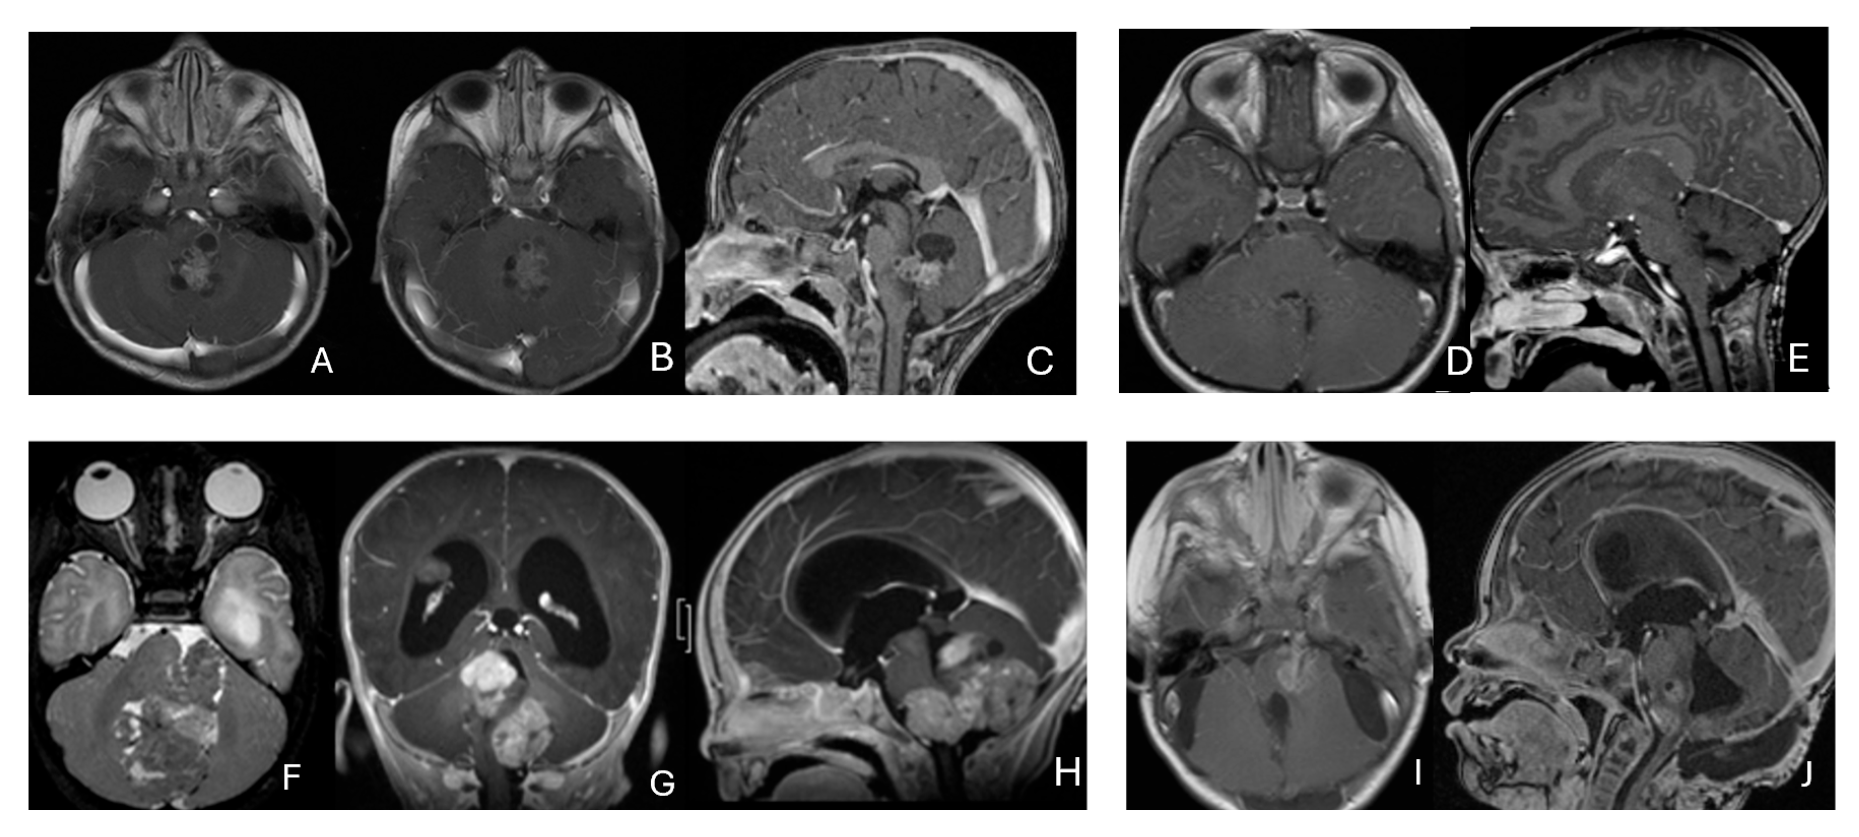

Eight patients had lesions localized to the CPA/CMF region (Figure 9). Among them, two had concurrent bilateral lesions. In one bilateral case, the lesions were asymmetric with questionable evidence of spinal cerebrospinal fluid dissemination, whereas another patient exhibited symmetric bilateral lesions.

Figure 9.

Cerebellopontine angle (CPA) ATRT. (A–E): T2-weighted MR images ((A), axial; (B), coronal) of a 7-week-old girl show a massive ATRT centered in the right CPA/CMF. Postoperative MR images ((C), axial; (D), coronal) show a gross-total resection of a highly vascular, necrotic mass. Intraoperative photograph following tumor resection illustrates key landmarks: LR, lateral recess; V, trigeminal nerve; VII/VIII, facial and vestibulocochlear nerves; IX/X, glossopharyngeal and vagus nerves. The cranial nerves were free of tumor. ATRT appeared to originate from the lateral posterior cerebellar lobe. (F–K): MR images ((F), axial; (G), axial) of a 3.5-year-old girl show bilateral CPA tumors: a larger, partially cystic mass on the left (open arrow) and a smaller solid mass extending toward Meckel’s cave on the right (solid arrow). The left-sided tumor was resected via a retrosigmoid approach ((H), axial; (I), axial). The lesion arose from the lateral cerebellar hemisphere and extended into the CPA cistern without cranial nerve invasion. Following chemoradiotherapy, the right-sided lesion resolved ((J), axial; (K), axial).

None of the CPA ATRTs showed evidence of cranial nerve origin at the time of surgical inspection (Figure 9E).

3.3. Pineal Region AT/RT

Eleven patients were diagnosed with ATRT in the pineal region, defined in the transverse plane from the posterior third ventricle to the quadrigeminal cistern, and in the vertical plane between the corpus callosum and the superior vermis. Of these, only one patient had a lesion centered in the posterior third ventricle that appeared to arise from the pineal gland (Figure 10A–D).

Figure 10.

Pineal region ATRT. (A–D): MR ((A), axial; (B), sagittal; (C), coronal) of a 3-year-old girl show an avidly enhancing ATRT in the posterior third ventricle. Postoperative post-contrast MR ((D), sagittal) demonstrates gross-total resection. (E–I): MR images ((E), axial; (F), sagittal) of a 13-month-old boy reveals a pineal region tumor extending from the quadrigeminal cistern into the fourth ventricle with obstructive hydrocephalus. The superior vermis and fastigium (open arrow) are depressed, and the tectal plate (solid arrow) is flattened and displaced rostrally. Gross-total resection of largely necrotic ATRT was achieved via a posterior interhemispheric transtentorial approach. Postoperative MR ((G), axial; (H), sagittal) shows restoration of the tectal plate (solid arrow) and fastigium (arrowhead). The superior vermis and the ependymal lining of the fourth ventricle were not invaded. A representative brain section (I) at post mortem study from another patient with a similar presentation demonstrates intact bilateral cerebellar peduncles (arrows) and a preserved tectal plate (arrowhead). Thus, the tumor is considered to arise from the superior medullary velum.

The remaining ten tumors of the pineal region, which constitute the majority, were found to originate from the superior medullary velum (SMV) [20,21]. Characteristic neuroimaging features included posterior displacement of the superior vermis and fastigium, as well as rostral displacement of the tectum, accompanied by a mass occupying the quadrigeminal cistern and the upper fourth ventricle (Figure 10E,F). Postoperative MRI following the resection of tumors arising from the SMV demonstrated preservation of both the cerebellar vermis and the tectum (Figure 10G,H). A postmortem examination of an ATRT involving the SMV revealed a defect in the roof of the fourth ventricle, with intact superior cerebellar peduncles and tectal plate—findings that strongly suggest an origin from the SMV (Figure 10I). Among the ten patients with SMV ATRT, eight exhibited central necrosis or varying degrees of cyst formation, while one patient presented with evidence of intra-tumoral hemorrhage. All patients with ATRT in the pineal region experienced hydrocephalus, and only one patient showed MRI evidence of subarachnoid dissemination at the time of diagnosis.

The mean age at diagnosis for patients with pineal region AT/RT was 12.4 months, with most cases occurring in infancy (approximately 9 months).